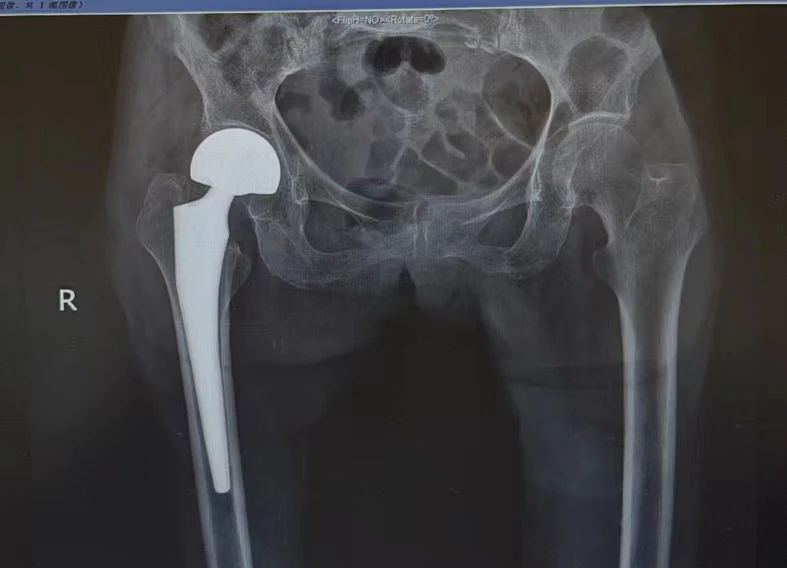

术后置换的右侧人工髋关节

在骨科与运动医学中心徐杰教授带领下,由骨科、麻醉科、手术室、护理等团队共同制定手术方案,邱美光主任医师、陈昱副主任医师为唐奶奶进行人工髋关节置换手术。在团队的密切配合下,手术顺利完成,术后第二天即可下地活动,充分彰显医院加速康复骨关节外科全国示范中心的优势。